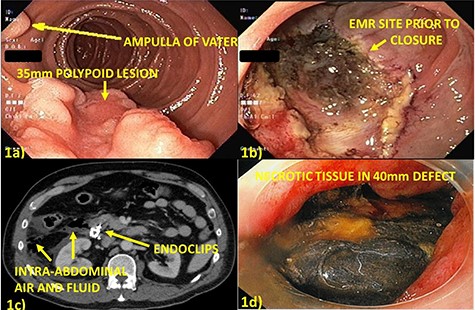

A 57-year-old male underwent EMR of a 35-mm polypoid lesion on the posterior wall of the second portion of the duodenum (Fig. 1a and b). This was complicated by intra-procedural bleeding (250 ml), which was stopped with epinephrine injection and Coagrasper (Olympus America, Center Valley, PA) application. The mucosal defect was closed with 12 endoclips (QuickClip Pro, Olympus America, Center Valley, PA). He developed evidence of perforation on post-procedure Day 1 (Fig. 1c and d) and was taken to surgery, the area irrigated and widely drained. Closure was not attempted due to severe thickening and friability of the duodenum.

(a) Thirty-five millimeters polypoid lesion on posterior wall of second portion of the duodenum, adjacent to the ampulla of Vater; (b) Mucosal defect after EMR of the lesion; (c) Computed tomography post-procedure Day 1 with free, intraperitoneal air and fluid adjacent in the right paracolic gutter and retroperitoneum suggesting perforation; (d) Endoscopy post-procedure Day 6 with 40 mm defect at site of prior closure, bile-stained necrotic tissue overlying retroperitoneum and free mucosal edges.